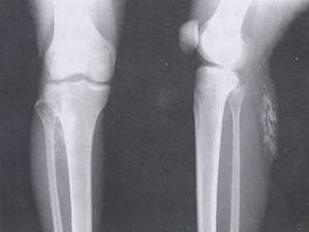

焦磷酸钙沉积病,是一种累及关节及其他运动系统的,与二水焦磷酸钙(calcium pyrophosphate sedimentation,CPPS)晶体沉积有关的晶体性关节病,因此,又称之为焦磷酸关节病。